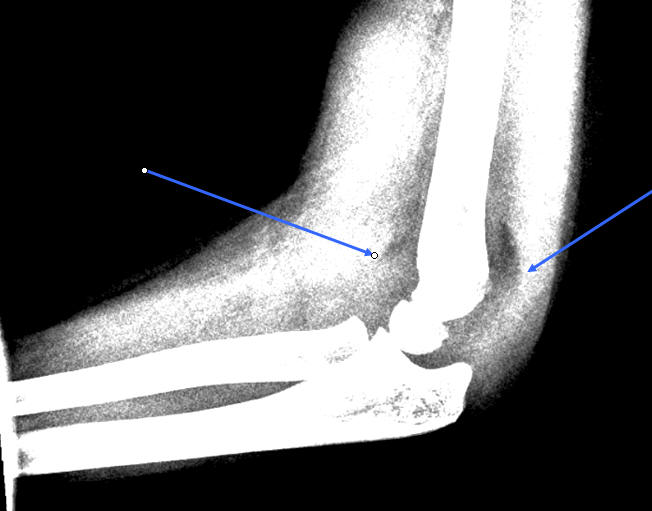

Dislocerede (se figur) frakturer behandles med reposition og osteosyntese med 2

Dislokation: En linie langs forsiden af humerus går normalt igennem midterste

1/3 del af capitulum humeri. Hvis hele capitulum ligger bagved denne linje skal

der reponeres og osteosynteres i GA. Hos børn under 4 år tillades lidt større